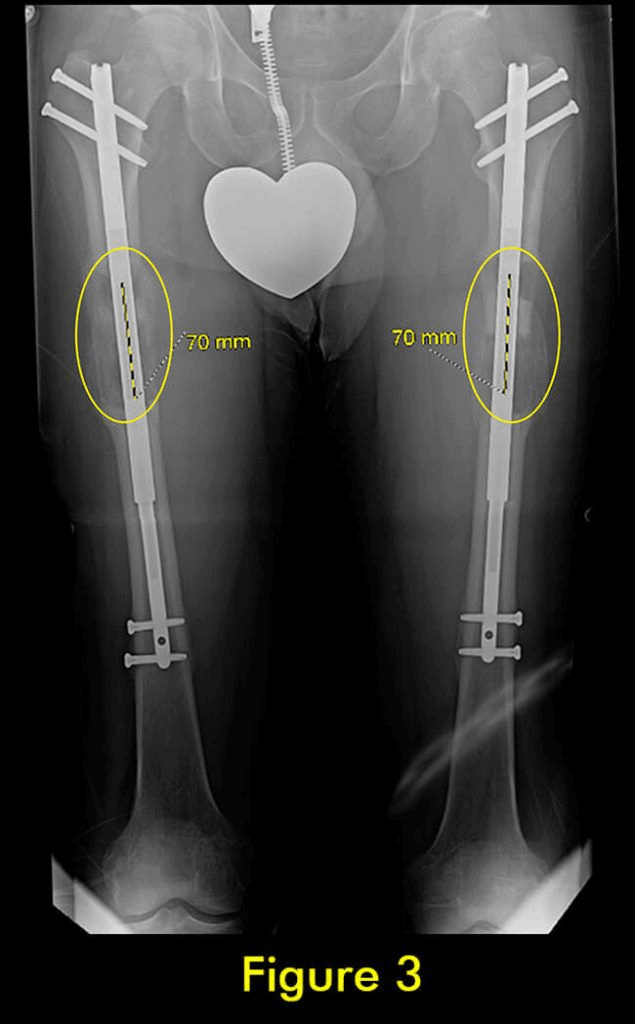

图1:延长量细微差异

过早合并示意图2

图2:X光片确认诊断

过早合并示意图3

图3:重复截骨术

过早合并示意图4

图4:完全巩固